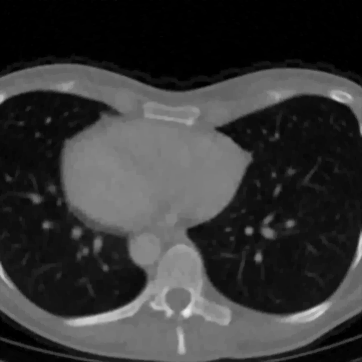

In Figure 12 we compare the PD3O reconstructions (top) and their corresponding errors with respect to the ground truth (bottom) using different regularization parameter choices , and for PD3O. Obviously, using the estimated parameter-map leads to a significant improvement of the reconstruction. In particular, sharp edges are retained, while using a constant regularizing parameter results in a significant blur. This can be also seen in Table 4, where we compare the NRMSE, PSNR, SSIM and blur and evaluated on the first 100 test images of the LoDoBaP dataset. These results are visualized in Figure 13 using box-plots. Note that the FBP seems to better than PD3O- in terms of the blur effect, but this can be explained by the fact that FBP reconstructions admit a lot of high-frequency artefacts leading to a small blur effect.

Further PD3O- reconstructions with their corresponding estimated parameter-maps are shown in Figure 14. Note that the parameter-maps are given in a logarithmic scale. As expected, the regularization is strong in constant areas and less strong on edges or finer details in order to reduce a smoothing in these regions.